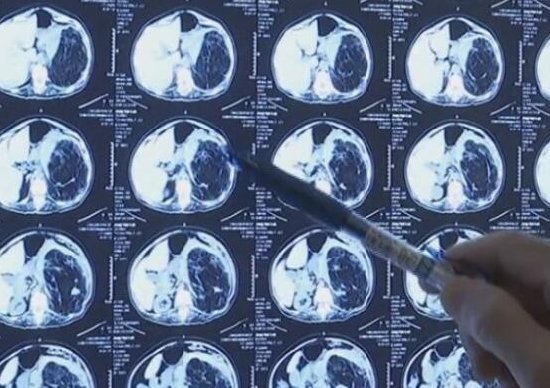

根据诊断结果,曾阿姨的腹部竟然长有肾错构瘤!多年的腰痛之谜终于揭开,但是此时的肾错构瘤已经非常大,并伴有出血的症状,当地医院不敢贸贸然做手术。

经过测量,从曾阿姨体内取出的这个瘤体长 25 厘米,宽 21 厘米宽,厚 11 厘米厚,重量达到 8 斤,医生表示,这么大的瘤体还是很少见的。